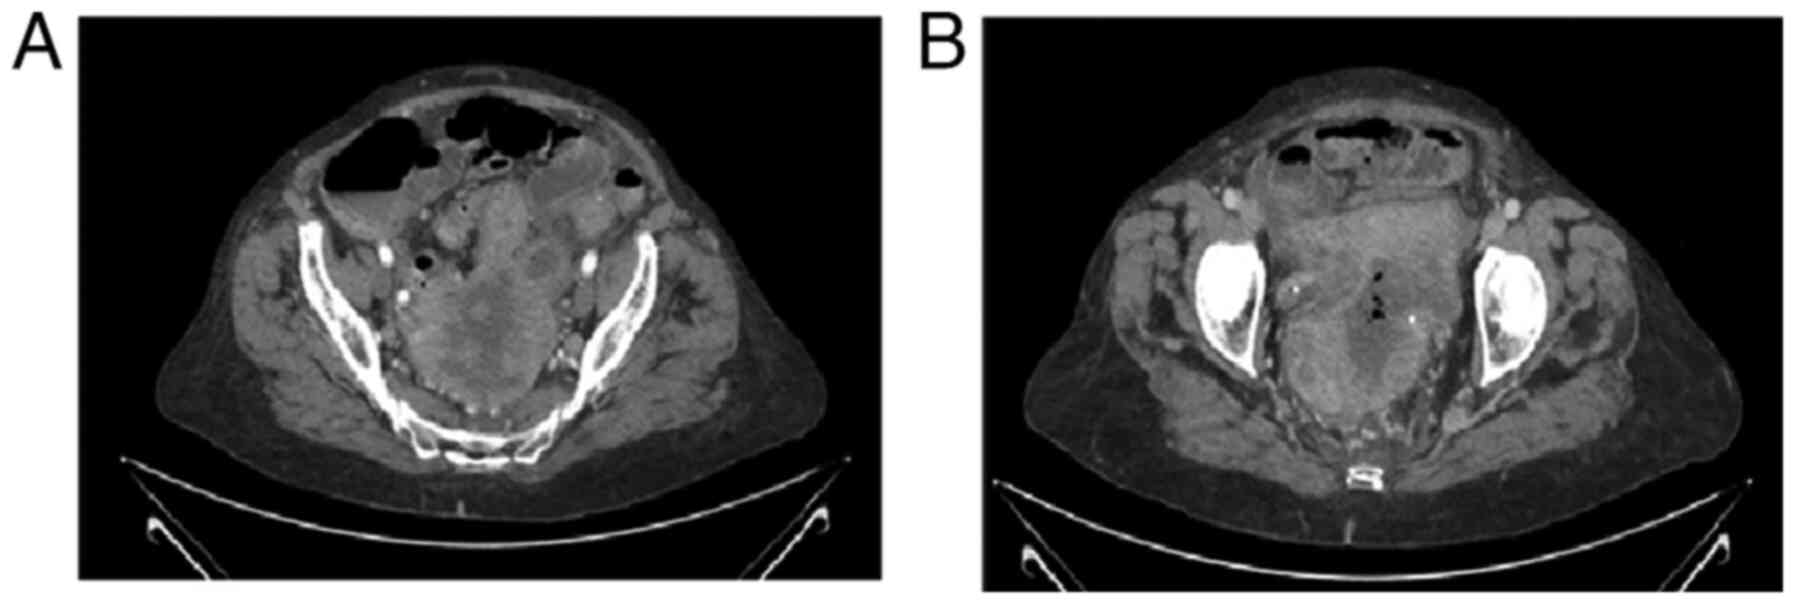

Uterine carcinosarcoma with intestinal involvement: A case report and literature review

Uterine carcinosarcoma (UCS) is a high‑grade endometrial cancer characterized by two components: Carcinomatous (epithelial) and sarcomatous (stromal tissue) elements. The present study describes a clinical case of this type of UCS and also provides a brief literature review of this type of tumor. A 72‑year‑old female visited the emergency department of the authors' hospital with pain in the hypogastric region, intestinal dysrhythmia since 3 months prior, fever and a palpable abdominal mass. Laboratory test results revealed sepsis and mild anemia and an imaging test revealed a large uterine tumor with wide areas of necrosis and adenopathies. As determined by the multidisciplinary committee, surgery was considered the main treatment option and this was performed with no incidences. Carcinosarcoma is a rare tumor, which most frequently occurs in older women. The diagnosis is based on symptoms and imaging tests, such as ecography and scans. The gold standard of treatment is surgery, although it is possible that other types of therapies, such as chemotherapy and radiotherapy may also be effective, depending on the tumor stage. On the whole, the prognosis of patients with this type of tumor is poor, with a low survival rate, even in earlier stages due to its malignant component and the possibility for metastasis. Surgery is the optimal treatment for this type of tumor, if this is possible, always individualizing patients.

Figure 1

Figure 2